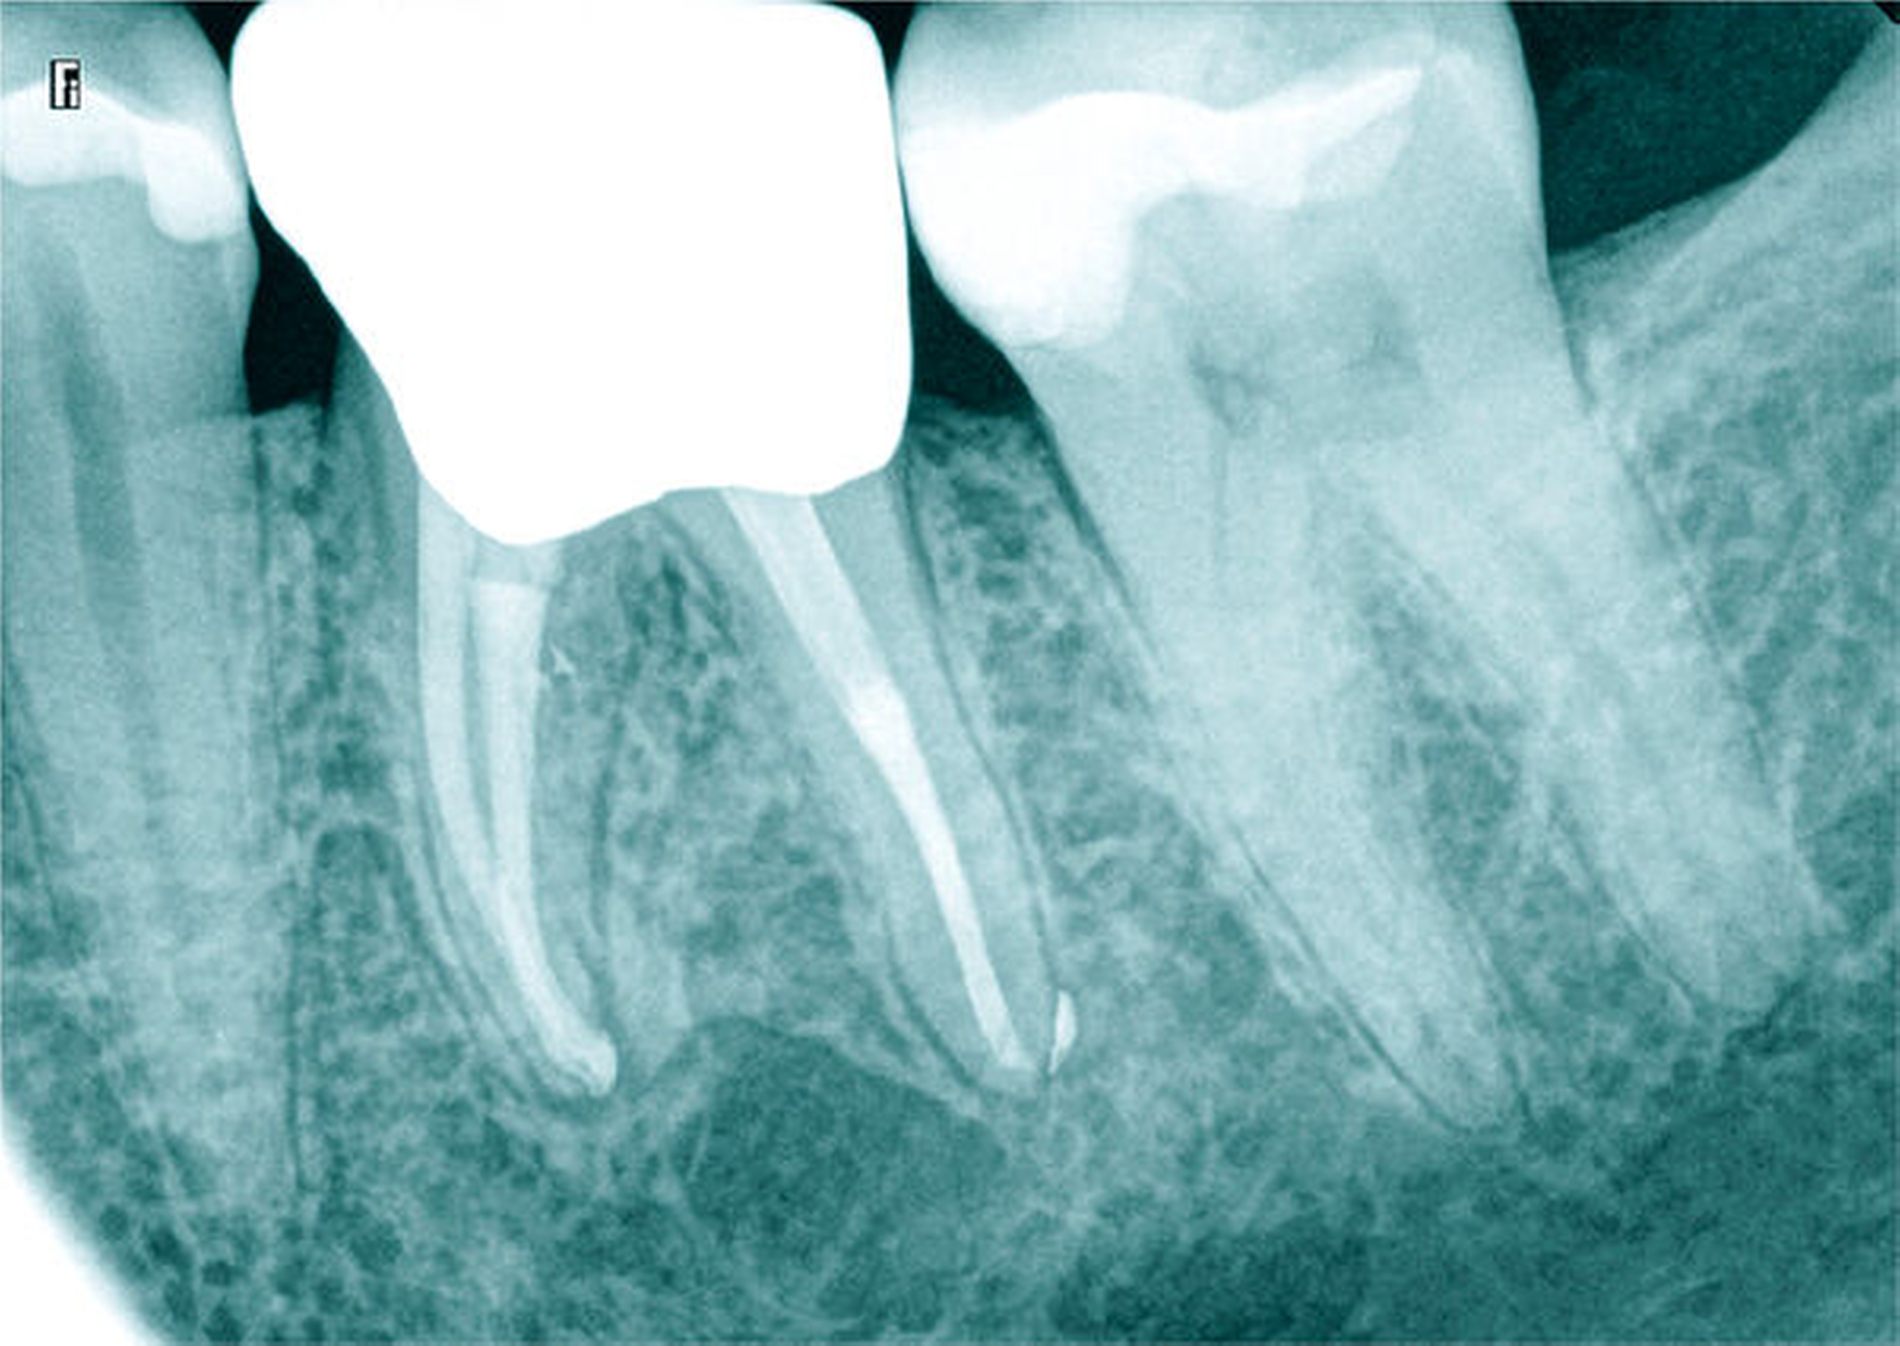

Röntgenbilder können genutzt werden, den anatomischen Schwierigkeitsgrad zu ermitteln. Lässt sich ein Wurzelkanal vollständig bis zum Apex mit einem Krümmungswinkel bis zu 30 Grad und einem großen gleichmäßigen Krümmungsradius erkennen, ist keine erhöhte Schwierigkeit in der Therapie zu erwarten (Abbildungen 1 und 2).

Krümmungsradius: Ist demgegenüber der Verlauf des Wurzelkanals unterbrochen, kann meist mit einer tiefen Wurzelkanalaufteilung gerechnet werden (Abbildung 3) [Reuver, 2002].

Lässt sich der Wurzelkanal auf der Röntgenaufnahme nur apikal erkennen, liegt meist eine Kalzifikation der Pulpa vor, die häufig erst unter Nutzung einer optischen Vergrößerung überwunden werden kann [Kiefner et al., 2017].